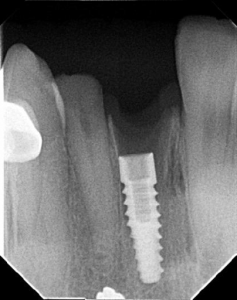

RADIOGRAFICAS PERIAPICALES Herramienta esencial para identificar implantes dentales LA CLAVE PARA IDENTIFICAR IMPLANTES. La identificación de implantes dentales sin información previa es una situación frecuente...

RADIOGRAFICAS PERIAPICALES Herramienta esencial para identificar implantes dentales LA CLAVE PARA IDENTIFICAR IMPLANTES. La identificación de implantes dentales sin información...